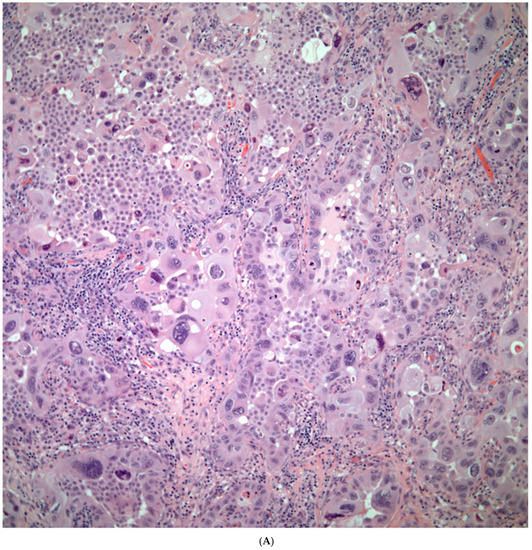

Giant Cell Carcinomas: These tumors may show predominantly a neoplastic cellular proliferation composed exclusively of multinucleated giant cells or a predominantly giant cell carcinoma (Figure 5A,B) or associated with a conventional non-small cell carcinoma like adenocarcinoma or squamous cell carcinoma. The giant cell carcinoma may show giant cells of the syncytiotrophoblastic, osteoclastic, or null cell type. The giant cell carcinomas of the null cell type characteristically show a prominent inflammatory background and giant cells engulfing inflammatory cells (emperipolesis) (Figure 6A,B). The tumors composed of osteoclast-like giant cells show giant cells like those described in bone tumors (Figure 7A,B).

Figure 6.

(A) Giant cell carcinoma, null cell type, note the inflammatory background; (B) Malignant giant cells with inflammatory cells and focal emperipolesis.